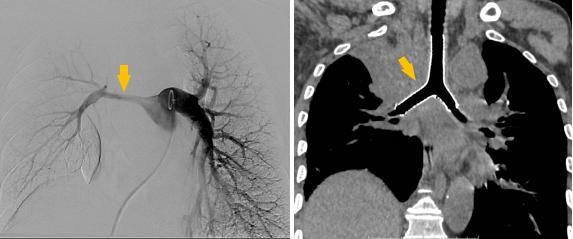

同期置入支架后狭窄明显改善

介入手术室里,一场无声的战役打响。麻醉科主任闫华凭借高超技术,成功为患者通气建立安全通路,为手术的实施奠定基石。介入科主任贺光辉带领团队细致操作,将一枚Y形气管支架在X线引导下输送至预定位置后精准释放,原本被肿瘤挤压得只剩一丝缝隙的气道被稳稳地撑开。紧接着一枚肺动脉覆膜支架置入到受压变窄的右肺动脉主干内并准确释放,再次造影,使得右肺动脉血流迅速得到改善。